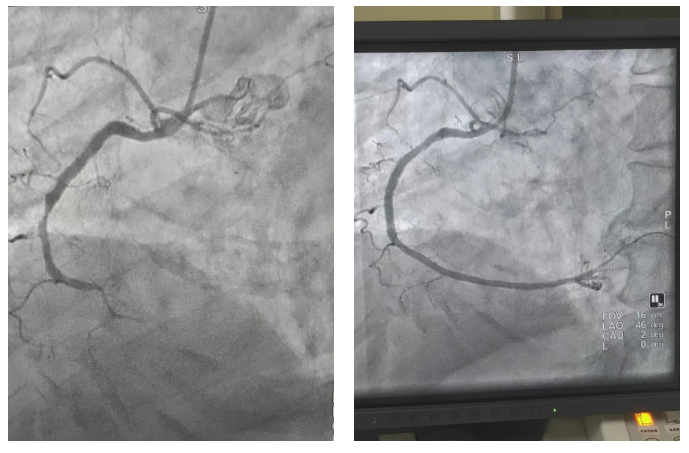

2月19日,祝阳镇卫生院接诊一名患者,仅表现为胸闷1小时,前一日夜间心电图还显示正常。基层医生敏锐捕捉到病情变化,将复查心电图上传至群内。王秀主任第一时间研判为急性下壁心肌梗死,指导立即启动急救流程。患者入院后造影显示右冠开口完全闭塞,介入团队迅速实施手术,成功开通血管,将患者从死亡线上拉了回来。

春节假期期间,胸痛中心先后完成8台急诊介入手术。其中,一名73岁老年女性因呕吐、上腹痛由祝阳卫生院转诊,看似胃肠症状的背后,实则是前降支完全闭塞。面对患者肱动脉严重狭窄、锁骨下动脉迂曲的复杂情况,介入团队迎难而上,更换手术途径,成功为患者植入支架,打通生命通道。